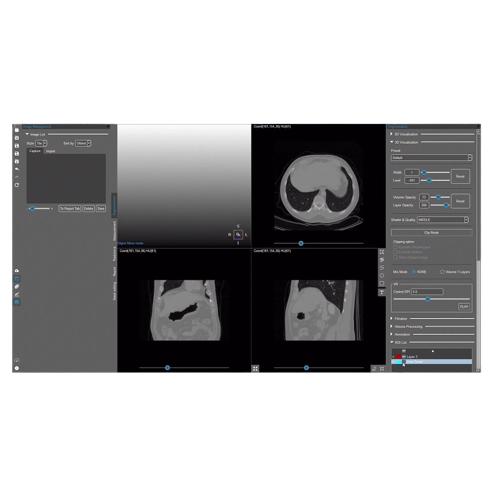

MEDIP PRO is a comprehensive software that processes medical images, enabling image analysis, 3-dimensional construction, modeling, and design with its automatic artificial intelligence (AI) segmentation technology at its core.

MEDIP PRO is equipped with One-Click Segmentation, which helps auto-segmentation

and extracts virtually all human body components in medical images (CT and MR) including patients’ organs and pathologic lesions.

and extracts virtually all human body components in medical images (CT and MR) including patients’ organs and pathologic lesions.